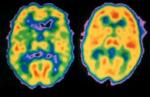

U Srbiji ima više od 40.000 pacijenata sa dijagnozom šizofrenije, a oporavak i tok bolesti zavise od redovnog uzimanja terapije, zaključeno je na konferenciji "Šizofrenija - bolest koja pogađa sve nas. Ne zatvarajte oči pred njom".

Šizofrenija je hronično oboljenje koje se obično javlja u adolescenciji ili ranim dvadesetim godinama, mada se, kako je rečeno, simptomi mogu javiti i u kasnijem životnom dobu.